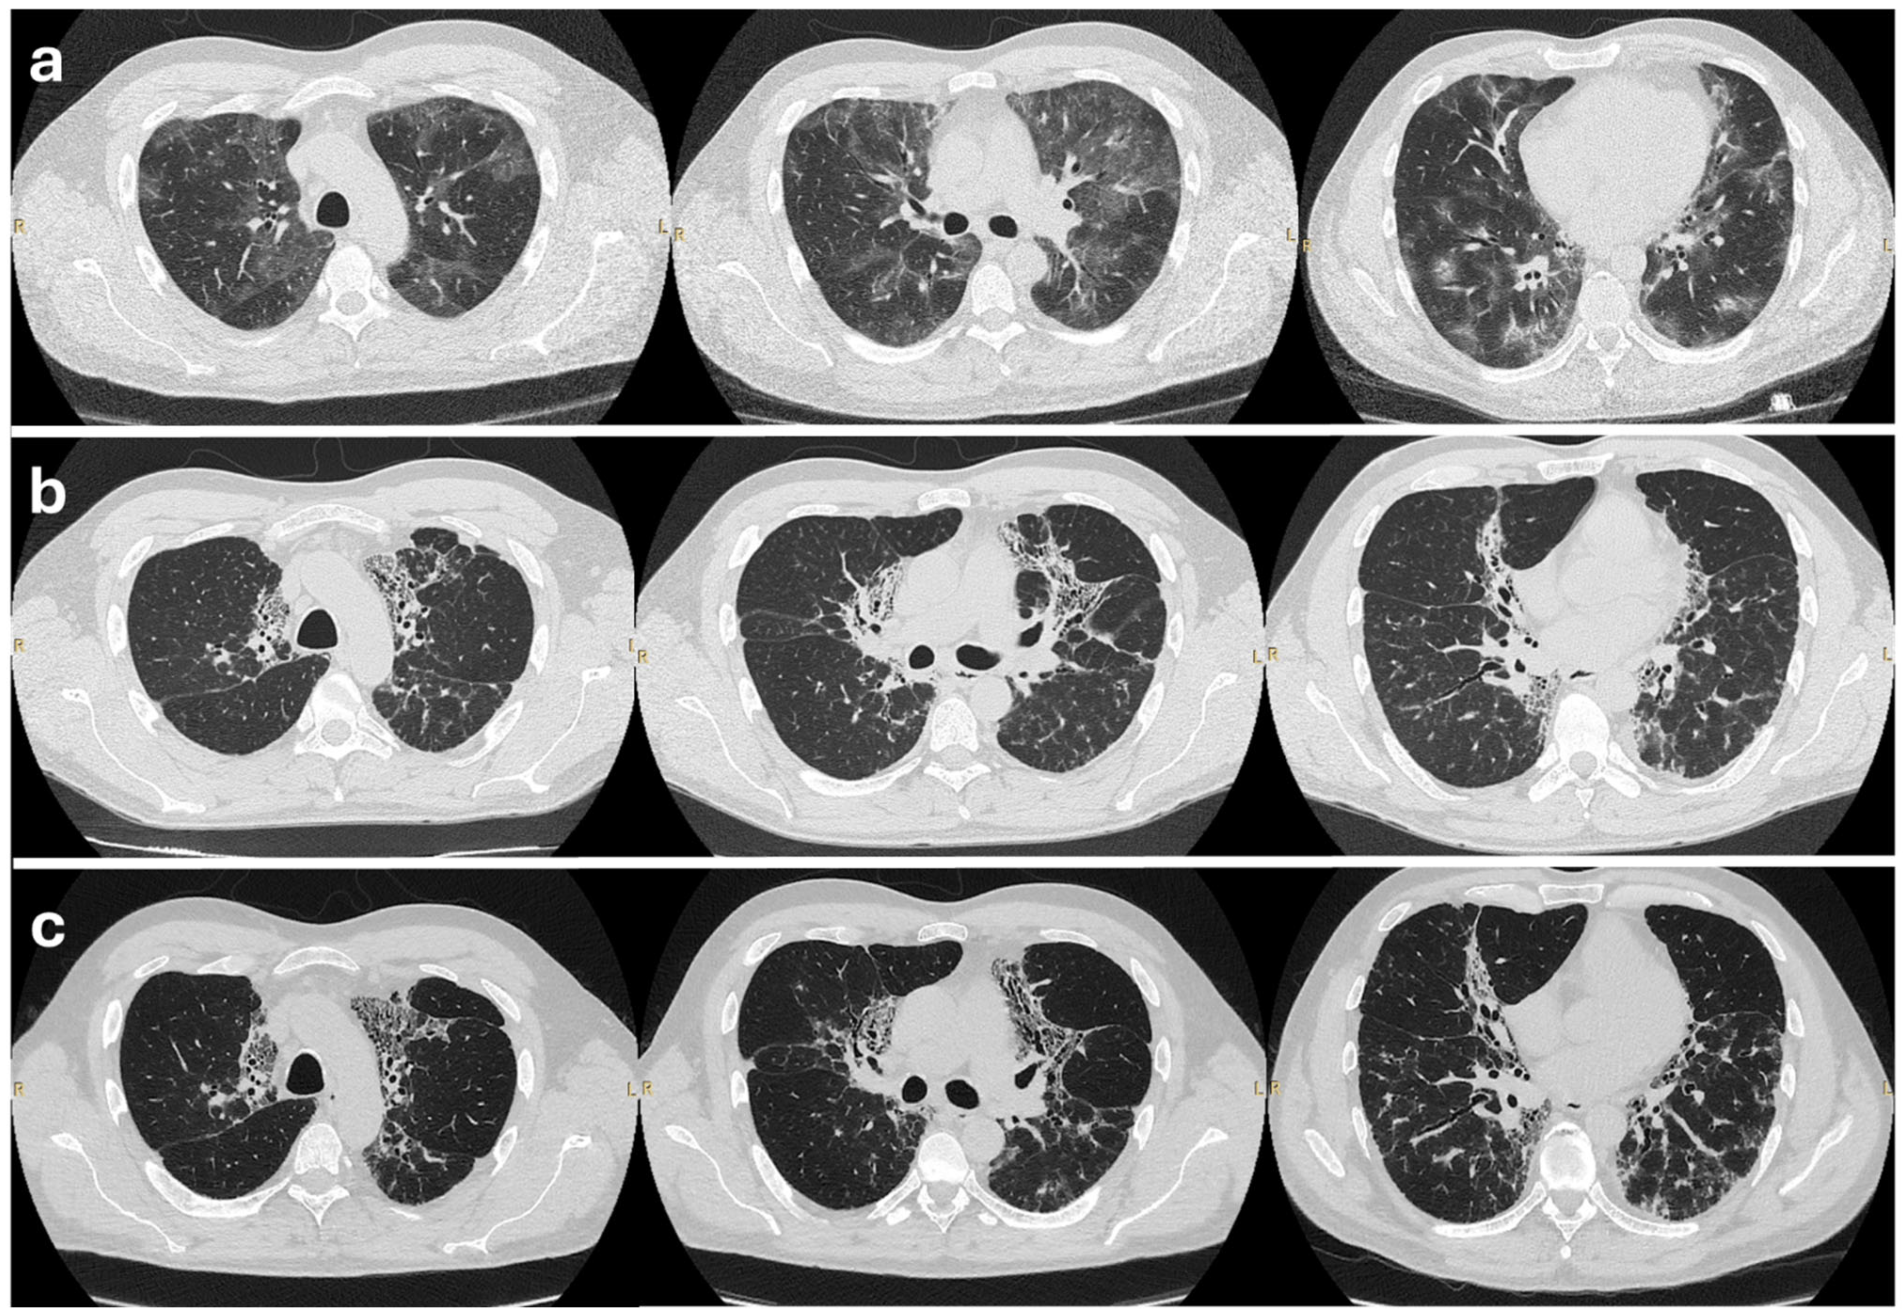

1. Introduction

2. Case Presentation

2.2. Initial Treatment and Outcome

2.3. Further Management

2.4. Outcome on Mepolizumab